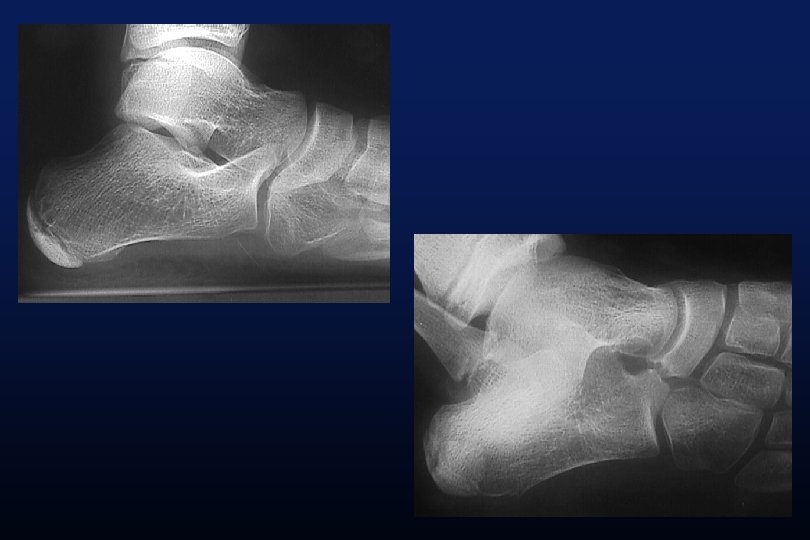

LES SYNOSTOSES DE L ’ARRIERE PIED Coalitions Tarsiennes (Tarsal Coalitions)

CALCANEO NAVICULAIRES (60%) TALO CALCANEENNES Synostoses et coalitions tarsiennes chez l'enfant. Étude de 68 cas chez 47 patients Ph. Rouvreau, J. C. Pouliquen, J. Langlais, C. Glorion, G. de Cerqueira Daltro The Too-Long Anterior Process Calcaneus: A Report of 39 Cases in 25 Children and Adolescents Pouliquen, J. C. M. D. ; Duranthon, L. D. M. D. ; Glorion, Ch. M. D. ; Kassis, B. Journal of Pediatric Orthopaedics Volume 18(3) June 1998 333 -336

Comfort 1998 Résection Coalition / surface sous talienne > 1/3 75% de mauvais résultats < 1/3 77% de bons résultats.